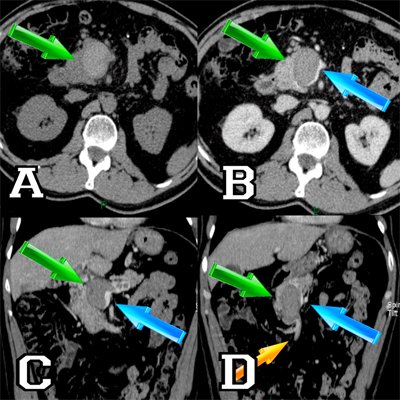

El AngioTC de abdomen evidencia una dilatación aneurismática de morfología fusiforme de 6x4x3,5 cm localizada en la vena mesentérica superior (VMS) en la confluencia portal. Se visualiza un trombo casi en la práctica totalidad de la misma que se extiende a la vena esplénica, porta, rama portal derecha hepática y vena gástrica. Acompañado de trastorno de la perfusión hepática y formación de vasos colaterales periportales. Ver Figura nº2: AngioCT abdominal (al final del artículo).

Figura 2: AngioCT abdominal

AngioCT abdominal:

A: Corte axial sin contraste: Imagen hiperdensa ovalada que corresponde a trombo de la VMS.

B: Corte axial en fase venosa: Defecto de repleción en vena mesentérica superior (VMS) con escasa permeabilidad del vaso.

C: Corte coronal en fase venosa: Trombo en vena esplénica.

D: Corte coronal en fase venosa: Trombo que no afecta a la porción distal de la vena mesentérica superior (VMS) y sus ramas. La flecha verde señala el trombo intraluminal. La flecha azul señala la luz de la vena. La flecha naranja marca las ramas de la vena mesentérica superior (VMS).